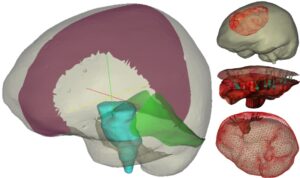

With respect to the presenting patient population, approximately 69,720 new cases of primary brain tumors are expected to be diagnosed in 2013 with approximately 35% of those tumors being malignant. Brain tumors are the second leading cause of cancer-related deaths in children under age 20, and males between the ages of 20-30. Interestingly, incidence rates are significantly higher in developed countries, approximately 70% higher. Five year survival rates following diagnosis of a primary brain tumor is approximately 33.8% on average but vary considerably with age (e.g. over the age of 65 is 10%). According to the National Cancer Institute surgical removal is the recommended treatment for most brain tumors with the goal of the most complete resection possible while preserving neurological function. With respect to the mission of the National Institute for Neurological Disorders and Stroke, more complete resection reduces the burden of neurological disease by restoring function, extending life, and improving the quality of that life. With respect to surgical therapy, the deployment of visual displays that relate the patient’s exposed brain within the operating room (OR) to the pre- operatively acquired neuroanatomical images has become commonplace. More specifically, surgeons can use a pen-like stylus to point at a specific feature on the patient’s brain tissue and see where that tissue resides on the neuroanatomical images as facilitated by an interactive display. One detriment to this process is when the patient’s brain deforms due to common surgical manipulations. As a result, the alignment between images and the patient’s physical brain becomes compromised and surgical error could ensue. Over years 1-7 of this award (initial submission & first renewal), we have demonstrated that intraoperatively acquired cortical surface geometric data can be used to: improve image-to-patient alignment, measure brain deformations during surgery, and drive a computational approach to brain shift correction during image-guided neurosurgery. In this application, we take the final step of extensive intraoperative validation and independent testing. The hypothesis to be tested is that computer models, cortical surface geometric data, and tracked stylus digitization technology when used to compensate for deformation during image-guided brain tumor surgery can predict the locations of eloquent brain surround pathology such that this approach is an effective surrogate to intraoperative magnetic resonance (iMR) imaging. The specific aims to accomplish this are to: (1) integrate a novel computer-vision based approach to surgical field digitization within the surgical microscope and commercial guidance environment such that acquired data can drive a computer model-based approach to correct displays for deformations, (2) conduct a 20 patient retrospective validation study with independent collaborator Dr. Alex Golby of Brigham and Women’s hospital comparing the results from our cortical surface deformation driven compensation pipeline to that acquired by the “gold standard” iMR imaging approach, (3) conduct two prospective 20 patient studies at Vanderbilt and the Brigham respectively, and evaluate intraoperative workflow, as well as the efficacy of corrected displays at institutions wit and without the presence of the iMR alternative. With respect to the importance of this work, in large part, the use of image-guided surgery for surgical resection in soft-tissue organs has been confined primarily to the cranial environment with the common understanding that ‘brain shift’ is a problem. With the resolution of deformations by this low-cost minimally encumbered solution, the ability to translate image-guided surgery to other soft- tissue organs could become commonplace. Furthermore, the approaches herein are inexpensive when compared to intra-operative imaging methods (e.g. MR), and scalable, i.e. capable of widespread adoption. This application could be seminal in providing the needed surrogate for the wider populations of patient that could benefit from improved ‘deformation corrected’ guidance but may not have access to iMR facilities.